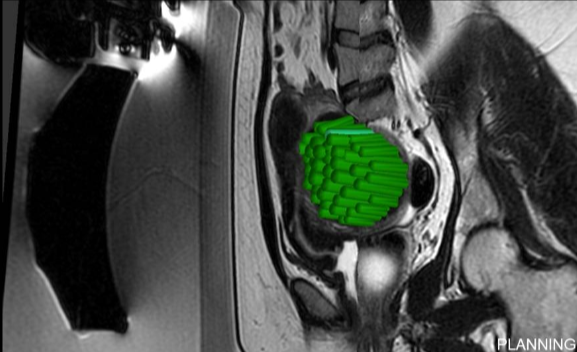

在开始该程序之前,会先进行手动分割操作。 随后,一款专用软件会自动制定出最佳的治疗方案。

在操作过程中,会进行多次超声波治疗,直至覆盖住足够的子宫肌瘤体积。 每次超声处理持续 20 至 40 秒,每次超声处理之间会有冷却时间(最长可达 90 秒)。 磁共振成像技术中质子共振频率的偏移特性使得能够监测每一个治疗点的温度。

经过治疗后,会进行核磁增强以评估被切除区域的范围。